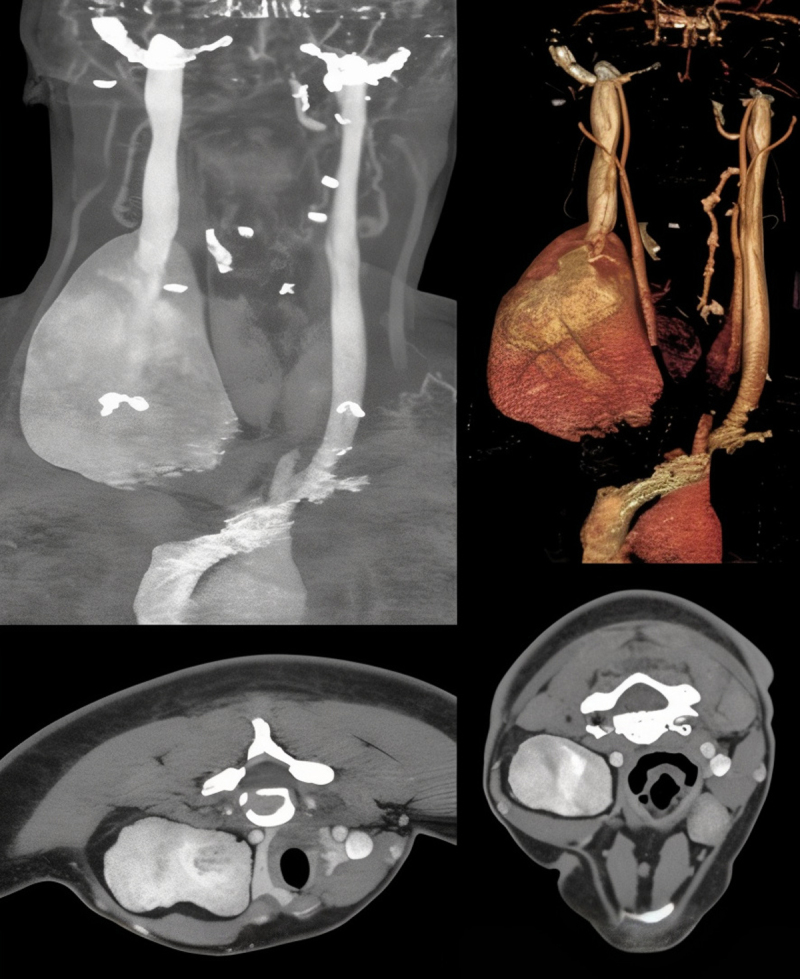

A 25-year-old female presented with a congenital painless growing mass on the right side of her neck with symptoms of tinnitus and difficulty breathing. Imaging revealed an aneurysm of the internal jugular vein reaching a maximum diameter of 9.2 cm, shifting the trachea and right thyroid lobe to the left side. Simple excision was sufficient to treat compression symptoms and prevent potential thrombosis and embolism. This is the first reported case of aneurysmal internal jugular vein with fibrofatty degeneration and hamartomatous wall morphology associated with compression symptoms.

25岁女性,颈部右侧先天性无痛性生长肿块,伴有耳鸣和呼吸困难。影像学显示颈内静脉动脉瘤最大直径达9.2 cm,气管和右甲状腺叶向左侧移位。单纯的切除足以治疗压迫症状,防止潜在的血栓形成和栓塞。这是首次报道的动脉瘤性颈内静脉纤维脂肪变性和错构瘤壁形态与压迫症状相关的病例。